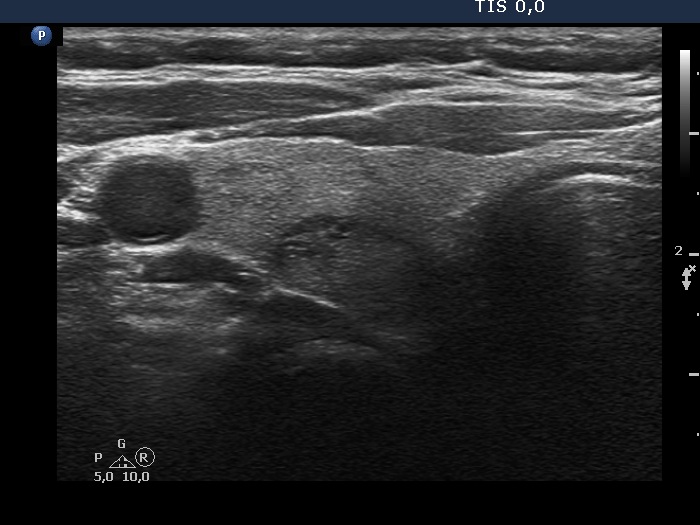

Ultrasonography. The thyroid was echonormal and had multiple nodules, mostly minimally hypoechoic or echonormal. The dimensions of the left lobe were 27x15x57 mm (12.1 mL in volume). This lobe had a minimally hypoechoic-echonormal nodule which presented halo sign. The dimensions of the nodule were 22x13x53 mm (7.93 mL in volume). Compared with the first examination for 17 years, the volume of the nodule increased by 23% while the nodule did by 43.9%. (The height of the patient was 168 cm, the weight was 86 kg.)